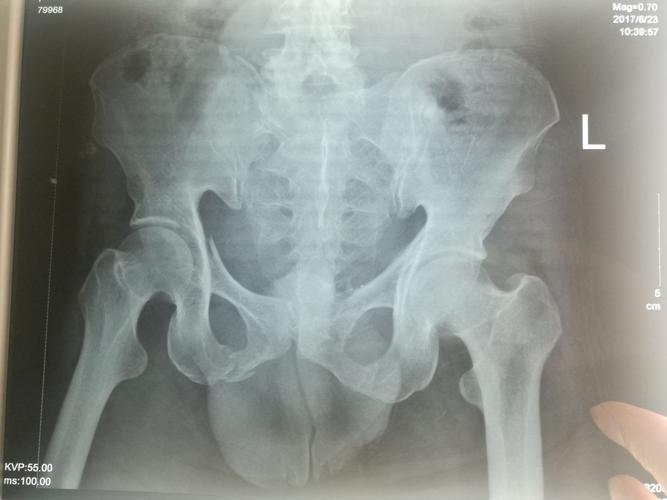

左侧坐骨支骨折图片

左侧坐骨支骨折图片,坐骨支骨图片

30 13:23:10坐骨支骨折 某男,48岁,因翻车砸伤骨盆,致左侧坐骨支骨折

男,49岁,骨盆,双侧耻骨坐骨支骨折!